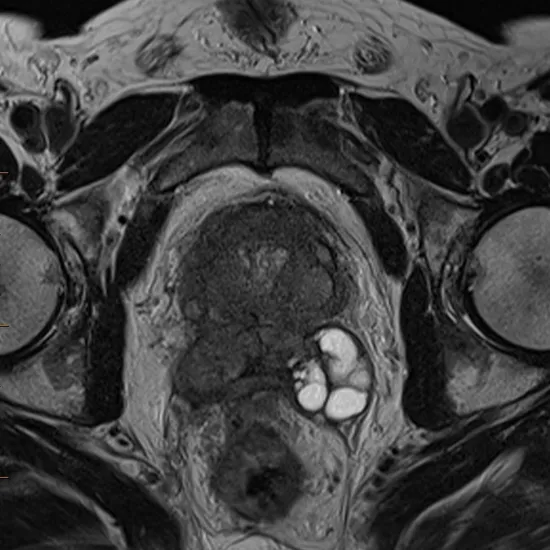

What is MRI Perfusion Prostate?

MRI Perfusion helps assess brain tumours, growths, infections, and vascular and degenerative illnesses. It helps grade tumours and evaluates treatment responses in stroke and cancer patients. Perfusion involves lymphatic or blood-vascular fluid transfer to an organ or tissue. MRI perfusion data can be used to compute blood-flow-related tissue characteristics.